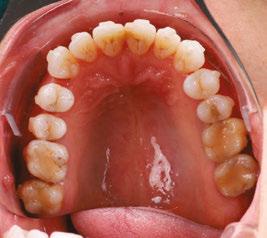

A visual screening tool validation study has recently been concluded and submitted to the Journal of Evidence-Based Dental Practice. This study is the collaboration of this author and the principal investigator Judith Owens, MD, funded by a grant from the American Academy of Craniofacial Pain (AACP). This study looked at the risk factors for pediatric sleep-disordered breathing (SDB) and craniofacial features, validated using the PSQ and a 22-item parent reported measure for SDB risk in children. Subject characteristics included age, sex, race, and ethnicity. Various craniofacial features were evaluated, such as: retrognathic mandible, open mouth posture, convex profile, midface deficiency, flat cheeks, concave profile, dolichocephalic face, frontal asymmetry, forward head posture, and rolled shoulders. It also included intraoral evaluation of: crowding of teeth, crossbite, narrow vaulted palate, crowding of upper teeth, narrow

palate, open bite, tongue thrust, crowding of lower teeth, narrow lower jaw, tongue tie, and “heart”-shaped tip of tongue. Twelve data collection sites across the U.S. were sourced to demonstrate ease of use, reproducibility, and which conditions had highest correlation. It was found that the following conditions had the highest correlation in decreasing order: forward head posture, narrow vaulted palate, open bite, tongue thrust, tongue tie, and heart-shaped tongue.